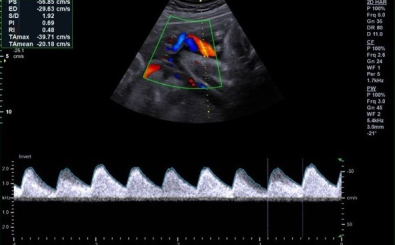

CLINICAL IMAGES

臨床影像

Abdomen

Directional Power Doppler Imaging